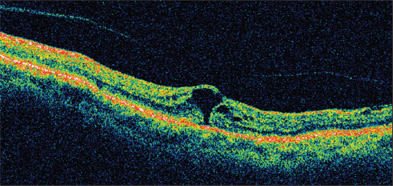

Figure 1. Stage 2 macular hole. Note the vitreous traction at the edge of the macular hole.

The classification system proposed prior to the optical coherence tomography (OCT) era is still used today, and the assumed mechanism has largely been supported by findings on OCT. In summary, stage 1 holes are not true holes but rather focal areas of vitreoretinal traction. Astage 1 hole has an equal chance to recover spontaneously as it does to progress to a stage 2 hole (full-thickness hole with vitreoretinal traction on the edge of the hole)(Figure 1). Once a stage 2 hole develops, there is little chance of spontaneous recovery, and surgical intervention is considered. Stage 3 and 4 holes are full-thickness holes, with the latter associated with a posterior vitreous detachment (Figure 2). Because studies suggest that the chance of visual improvement and anatomic success is higher if the surgical repair is performed within 6 months, it should not be delayed beyond this time frame.2